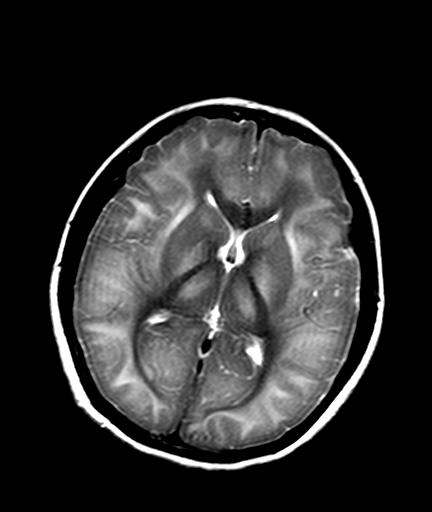

发热、头痛伴精神异常1周

较对称性脑白质异常信号,深部白质t2明显低信号(铁质沉积过多?)

考虑脑白质病变,请结合临床病史及实验室检查进一步分析。